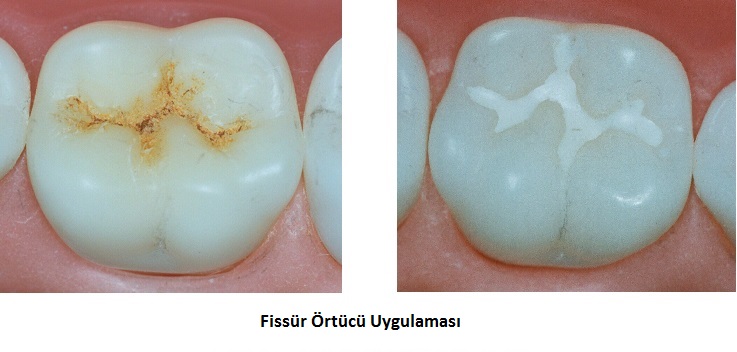

Fissür Örtücüler (Fissur Sealant)

Azı dişlerinin çiğneyici yüzlerinde dar ve derin oluklar (fissür) bulunur, yapıları itibarıyla temizliği zor olan bu bölgeler çürüğe elverişlidir. Özellikle ilki 6 yaşlarında süren daimi azılar gerekli tedbirler alınmadığı taktirde kolayca çürüyebilirler. Bunu önlemek amacıyla fissür örtücülerden yararlanılır. Dişlerin bu bölgeleri ince bir hat şeklinde fissür örtücülerle kapatılarak, gıda tutunmasını engelleyecek, kolay temizlenebilir bir yüzey elde edilir ve çürüğe direnç artırılmış olur. Uygulama çok kısa sürer, anestezi gerektirmez. Çocuğun diş hekimiyle tanışması ve güven duyması açısından önemli bir adımdır.

Fissür örtücü nedir, her çocuğa yapılmalı mı?

Fissür örtücüler, azı dişlerinin çiğneme yüzeyindeki derin olukların ince bir koruyucu tabaka ile kapatılmasıdır. Çürüğe karşı %80 koruma sağlar. Özellikle 6 yaş dişlerine (daimi azılar) mutlaka uygulanmalıdır. İşlem anestezi gerektirmez ve sadece birkaç dakika sürer.